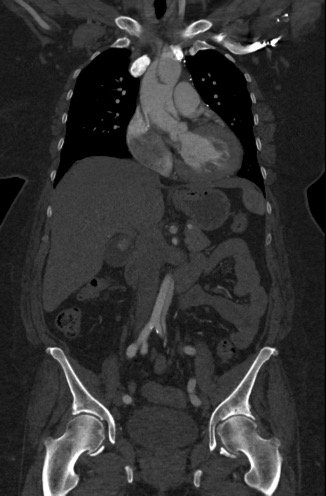

Because aortic dissection was suspected, the patient underwent urgent computed tomography (CT) angiogram of her chest, abdomen and pelvis that revealed her diagnosis.

The patient was found to have a Stanford type A dissection (see yellow arrow) with visible false lumen starting at aortic arch (see green circle). The dissection extended into the descending aorta (see blue circle) as shown by the false lumen (red highlighted area) visible on CT. The radiologist performed a reconstruction of the aorta, which showed that the left kidney was not being perfused, making the kidney not visible on the reconstruction.